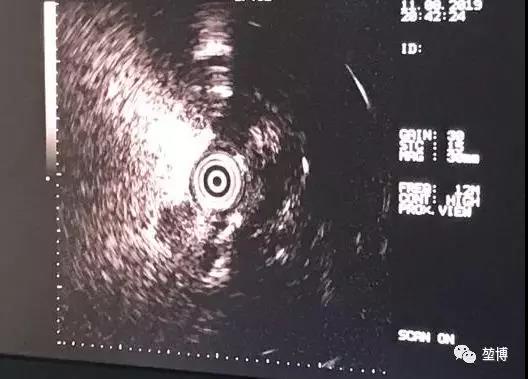

送入超声探头

超声确认抵达病灶